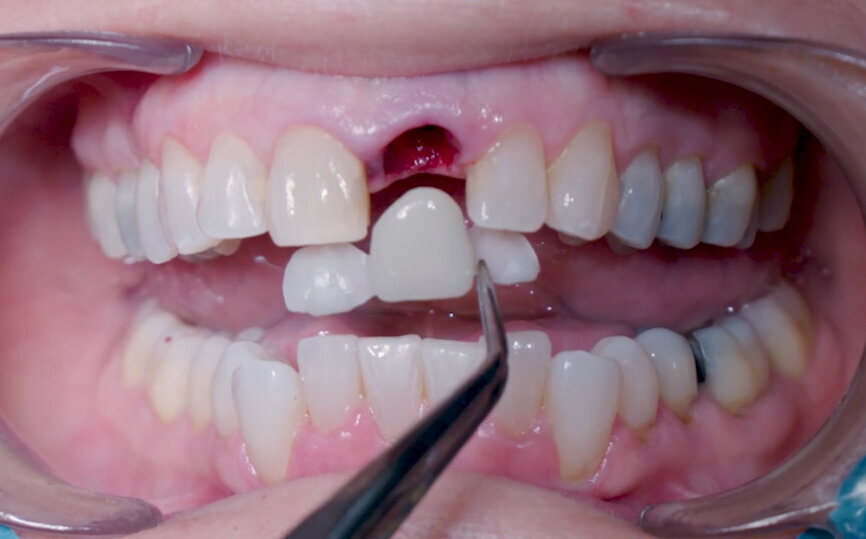

A 53-year-old female patient presented to the office with a fractured left central incisor which had been repeatedly bonded to a ceramic crown (Figs. 1 & 2). Anamneses and examination established good systemic and oral health, a well-balanced occlusion and no smoking habits. Cone beam computed tomography (CBCT) and a periapical radiograph showed external root resorption with very limited insertion into the alveolar bone, insufficient for adequate conventional intra-radicular post placement (Figs. 3 & 4). Considering that the fractured tooth was in the aesthetic zone, the patient requested restoration in the safest and fastest way possible.

Fig. 1: Initial situation, extra-oral view.

Fig. 2: Initial situation, intra-oral view.